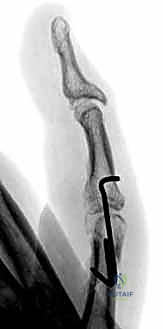

1. الرد المغلق والتثبيت بأسلاك كيرشنر (CRPP - Closed Reduction and Percutaneous Pinning):

تُعد هذه الطريقة الأقل توغلاً. يقوم الدكتور هطيف برد الكسر يدوياً تحت توجيه جهاز الأشعة السينية المباشر (C-arm) في غرفة العمليات، ثم يقوم بإدخال أسلاك معدنية دقيقة (K-wires) عبر الجلد لتثبيت العظم.

* المزايا: لا تتطلب شقاً جراحياً كبيراً، تحافظ على الإمداد الدموي للعظم، وتقلل من خطر التصاقات الأوتار.

* العيوب: تتطلب إبقاء جزء من السلك خارج الجلد (عادةً)، مما يستلزم إزالتها في العيادة بعد 4-6 أسابيع.